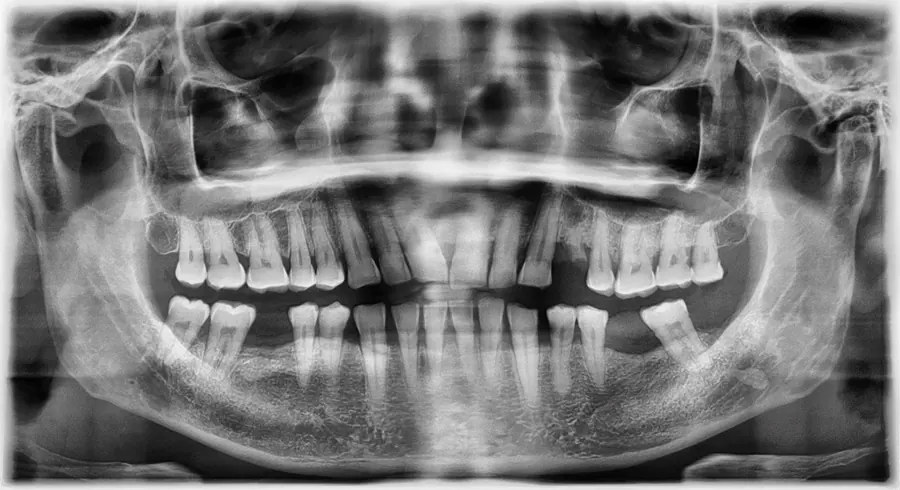

SERVICIOS RADIOLÓGICOS

Somos una clinica siempre a la vanguardia, Tiene para todos sus pacientes que deseen su Laboratorio de Radiología con la tecnología de punta lo más avanzado de México y el Mundo, que ya no requiere de escaneo, proceso selectivo, revelado, ni productos químicos, además ofrece mínimos niveles de radiación.